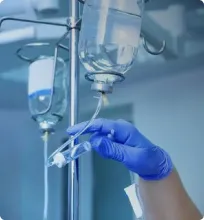

Прием препаратов

Лечение фобий фармакологическим способом считается основным при таких расстройствах. Медикаменты купируют острую симптоматику отклонения, нормализуют психоэмоциональное состояние. По назначению врача могут приниматься разные медикаменты. Специалист не только прописывает лекарства, но и предоставляет советы по лечению.

Фобические расстройства лечатся:

- Антидепрессантами. Они начинают действовать спустя 4-8 недель. Чтобы исключить появление побочных эффектов, сначала назначается небольшая дозировка. Со временем она повышается с учетом переносимости препарата. Нервные клетки обмениваются информацией с мозгом. В качестве проводников используются химические вещества, которые принимают участие в формировании ощущения страха, тревоги, стресса. Это связано со снижением серотонина (гормона счастья). Благодаря антидепрессантам подавляется тревога, нормализуется давление, улучшается состояние сердца.

- Транквилизаторами. Успокоительные средства помогают для лечения фобического расстройства, чувства страха, тревоги, паники. Препараты принимаются маленькими курсами. Их успокаивающий эффект связан с тормозящим воздействием на мозг. Также препараты расслабляют мышцы, снимают напряжение.

- Снотворными. Они нужны пациентам, страдающим бессонницей. Медикаменты принимают короткое время (до месяца) перед ночным сном.

У всех препаратов есть свои побочные действия. Также они отличаются привыканием. Поэтому медикаменты внимательно подбираются врачом с учетом состояния пациента. Тогда лечение фобий, страхов оказывается эффективным.